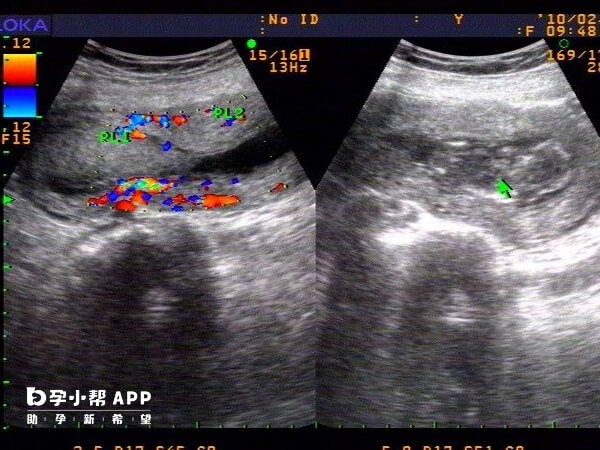

输精管缺如,是指单侧或双侧输精管完全或部分缺失。 由于输精管参与了输送精子的过程,因此双侧输精管缺如患者,可表现为男性阻塞性无精子症口(由于无输精管而导致精子运送途径阻塞)和不育症。

双侧输精管缺如的患者,一般通过睾丸穿刺或附睾穿刺取精,通常可获取精子,成功率较高(接近100%),但需结合辅助生殖技术(如试管婴儿)实现生育。